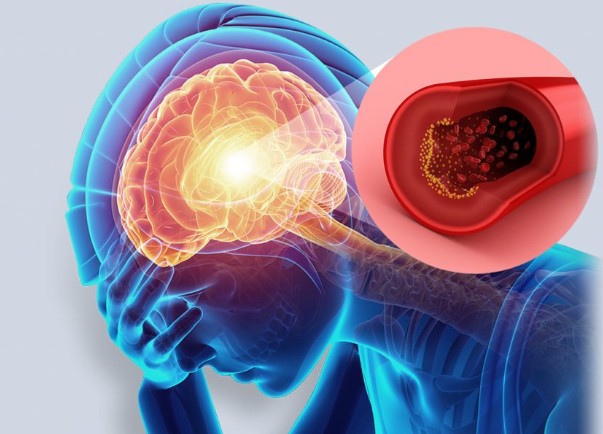

뇌출혈은 뇌혈관이 파열되어 뇌에 출혈이 발생하는 질환으로, 매우 급격하게 발생할 수 있으며 생명에 위협을 줄 수 있습니다. 하지만 뇌출혈이 발생하기 전에 나타날 수 있는 전조증상을 잘 인식하고 빠르게 대처하는 것이 중요합니다. 아래에 뇌출혈의 11가지 전조증상을 아주 자세히 설명하겠습니다.

뇌출혈의 가장 흔한 전조증상 중 하나는 심한 두통입니다. 갑작스럽고 강렬한 두통이 발생하며, 평소 경험하지 못한 매우 심한 통증을 느낄 수 있습니다. 이는 뇌에 출혈이 발생하면서 뇌압이 급격히 증가하기 때문입니다. 종종 "내가 겪어본 두통 중 가장 심한 두통"이라고 표현되기도 합니다.